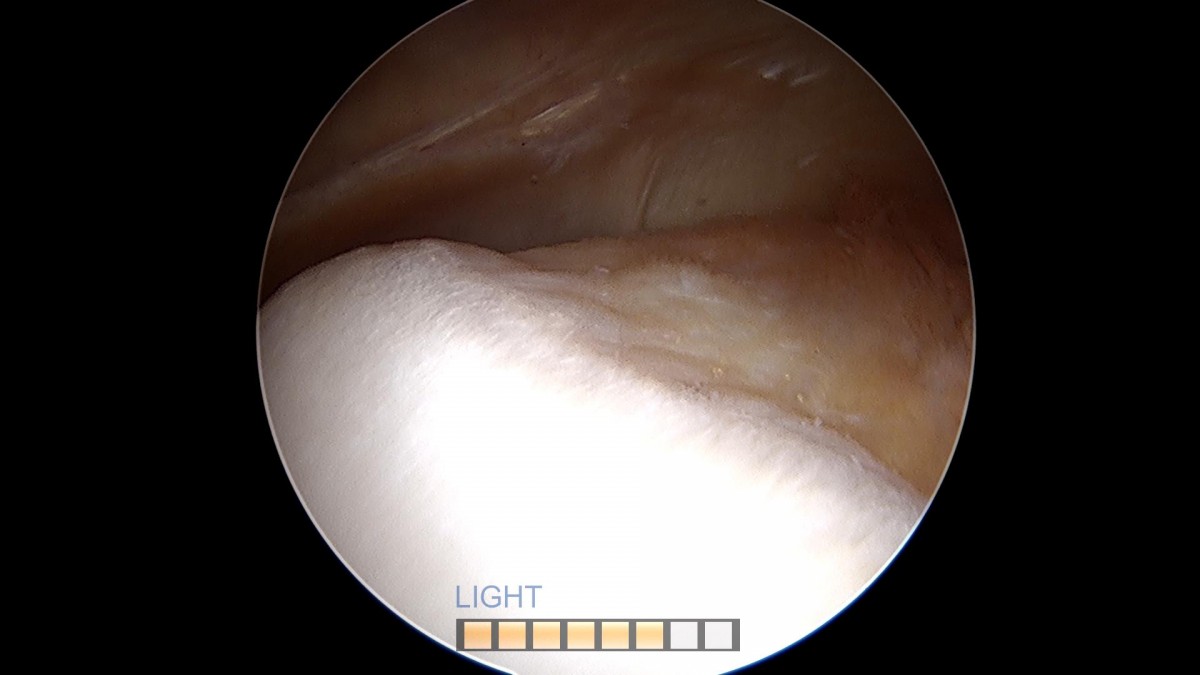

배우한원장님 무릎 경골 교정술 및 반월상 연골판 절제술 (1779)정미O 환자